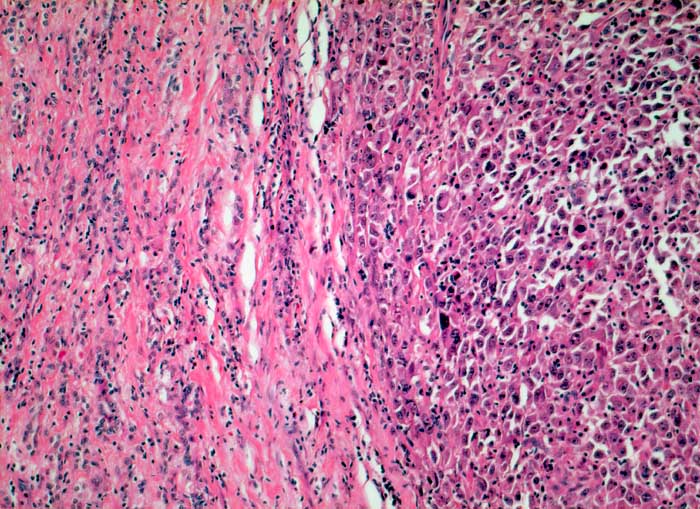

Abstriche von anaplastischen Karzinomen sind gewöhnlich sehr zellreich ausser bei ausgeprägter Desmoplasie. Die Grösse und die Form der Tumorzellen ist äusserst variabel. Oft finden sich sehr grosse, bizarre und spindelförmige Zellen. Die Kerne weisen offensichtliche Zeichen der Malignität auf: irreguläre Kernmembran, grobes dunkles Chromatin und Makronukleolen. Mitosen, auch atypische, sind häufig. Das Zytoplasma variiert von blass und vakuolisiert über granulär bis dicht. Nekrosen, neutrophile Granulozyten und eine Tumordiathese im Hintergrund sind typisch. Die Tumoren exprimieren Vimentin und Zytokeratine, sind aber negativ für Thyreoglobulin und TTF1 (Thyroid Transcription Factor).